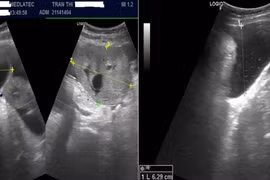

Bệnh nhân 41 tuổi được chẩn đoán ung thư buồng trứng qua xét nghiệm và hình ảnh, nhấn mạnh tầm quan trọng của kiểm tra định kỳ để phát hiện sớm.